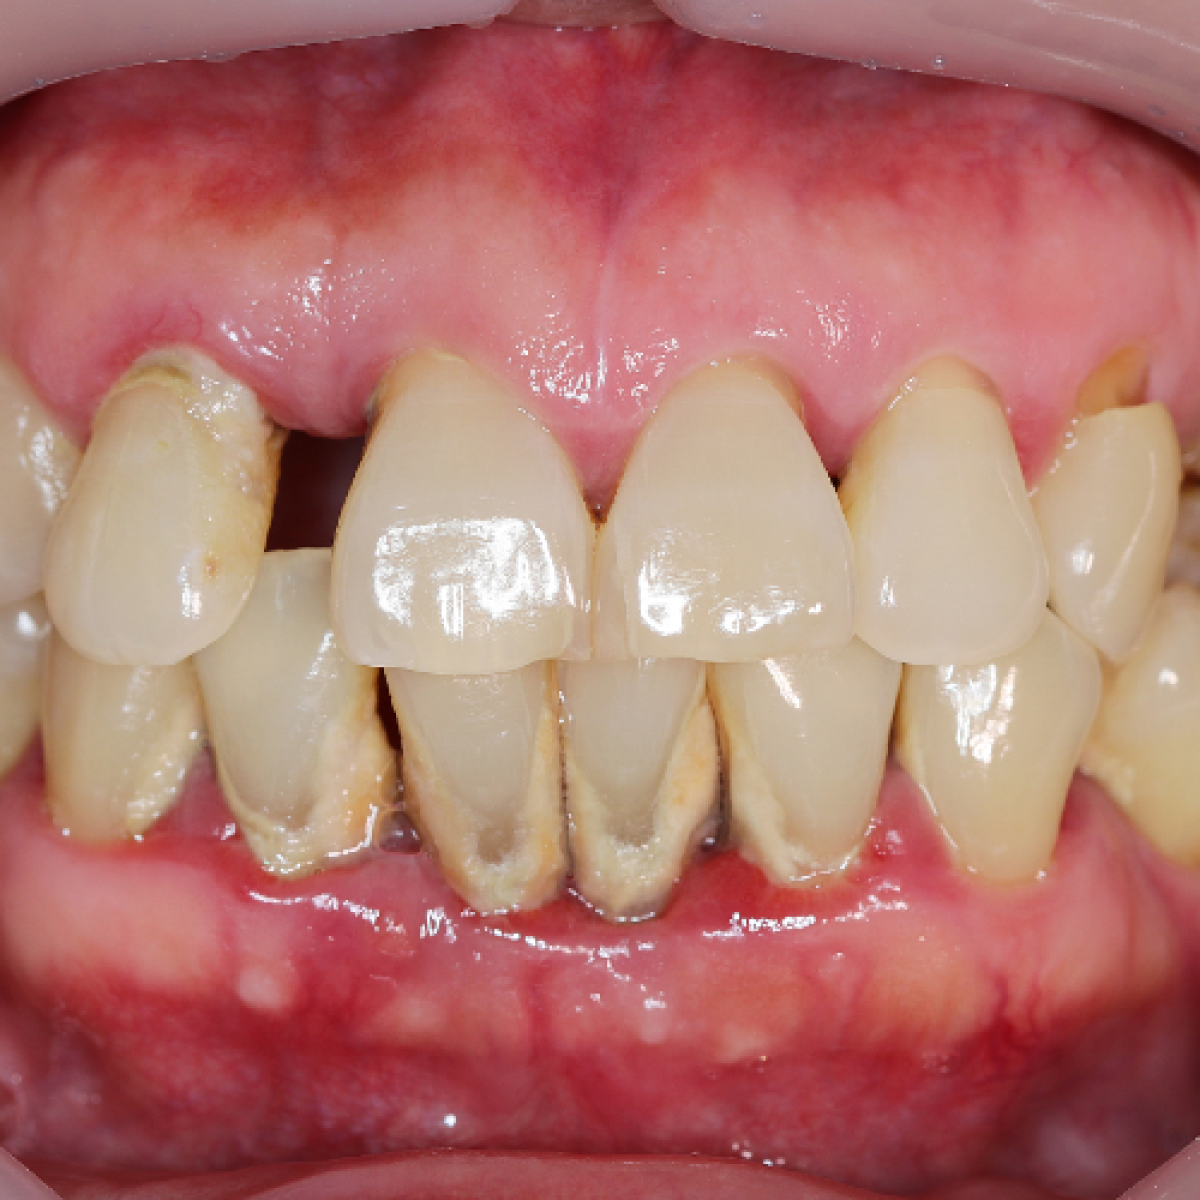

The aim of this study is to evaluate the periodontal status of patients with indications to zoledronic acid therapy for oncological diseases through the application of the New 2017 Classification of periodontal and peri-implant disease.

Periodontal evaluations were assessed to patients at the Dental Clinic of Padua for the preventive odontostomatological visit to zoledronic acid therapy (Zometa®) (Casi Group). The first group was then compared with a second group comparable in age, gender, diabetes, smoking and systemic diseases not related to the pathology for which therapy with zoledronic acid (Zometa®) (Control Group) was indicated. The computerized periodontal file of the University of Bern was used to record the periodontal parameters. Each patient, during the visit in the presence of imaging, through the use of a Williams and Nabers periodontal probe, was assigned a periodontal status assessment referring to the new 2017 classification of periodontal and peri-implant diseases during the visit. In the Casi Group an average BoP (%) equal to 25.26 and an average percentage presence of plaque (%) equal to 35.53 was detected while in the Controls group an average BoP (%) was detected 35.73 and a percentage presence of plaque (%) average equal to 25.46. The difference in BoP (%) and Plaque percentage presence (%) is statistically significant. The results of the application of the new classification of periodontal and peri-implant disease showed that, in the Cases group, 6.67% of patients had a state of health, 16.67% was associated with stage 1, 3.3% is been associated with stage 2, 40% were associated with stage 3 and 33.33% with stage 4. Grade A was associated with 57.14% of patients in the Cases group, Grade B with 35.71% and 7.14% grade C. The extension of periodontal disease in the Cases group was generalized in 47.37% of patients and localized in the remaining 55.56%. The results of the application of the new classification of periodontal and peri-implant disease showed that 6.67% of patients in the Controls group were in a state of health, 3.33% were associated with stage 1, 16.67% were associated with stage 2, 43.33% was associated with stage 3 and 30.00% with stage 4. Grade A was associated with 35.71% of the Control group patients, grade B with 60.71% and 3.57% grade C. The extent of periodontal disease in the Controls group was generalized in 52.63% of patients and localized in the remaining 44.44%. The comparison between the results derived from the application of the new periodontal classification carried out through the Fisher's Test, showed that there is no statistically significant difference between the two groups (p> 0.05). This result shows how the periodontal status of patients with indications for zoledronic acid therapy for oncological diseases reflects that of the general population.

The new periodontal classification classify patients based on risk factors and periodontal status and the risk of progression of periodontal disease, this allows to obtain a univocal evaluation that facilitates the sharing of data between clinicians and allows a good management over time of patients.